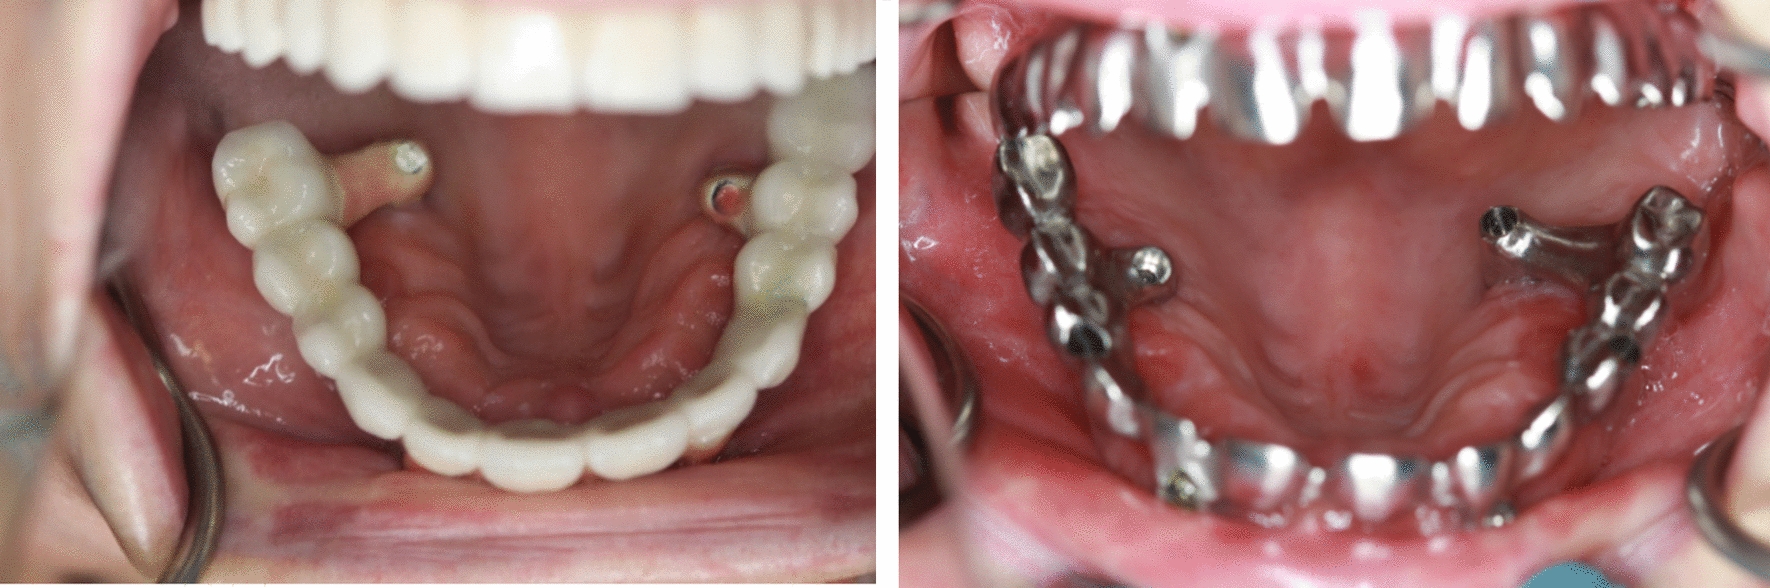

Offset of the Prostheses [O]

The emergence of zygomatic implants in the palate may lead to prostheses with "piping". Occasionally, a substantial dental bridge on the palatal side can cause discomfort, impacting speech, and limiting hygiene access (Fig. 10). Conversely, placing the implant too buccally can result in zygomatic implant failure (Fig. 11).

Fig. 10

The emergence of zygomatic implants in the palate may lead to prostheses with "piping"

Stella’s Method

Another risk of zygomatic implants is maxillary sinus inflammation. To prevent or at least reduce this risk, zygomatic implants should be placed extrasinusally or extramaxillary. Such an approach to osteotomy preserves the Schneiderian membrane. In the extramaxillary approach, multi-units attached to the implant nest are positioned at or near the top of the alveolar crest in the most convenient location. [31, 32] The main disadvantage of this method is the high risk of dehiscence of the zygomatic implant within the maxillary sinus as a result of Schneiderian membrane’s rupture during surgical procedure. However, its primary advantage is the preservation of alveolar bone. As a result, the risk of dehiscence is much lower because the gingiva lies directly on the bone and not on the implant. With this method, however, there is a risk that the position of the zygomatic implant head may not be ideal. The authors determined that the risk of palatal placement of the zygomatic implant head poses less danger in the long run than the dehiscence of the zygomatic implant. Thus, to prevent or at least mitigate this risk, the authors of the article opted to place implants using Stella's method (Fig. 12).

Fig. 12

a Intrasinusal and extramaxillary and b intrasinusal and intramaxillary implant placement according to the Stella technique